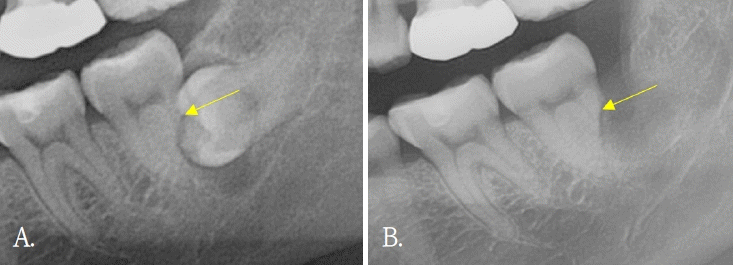

Figure 2.

Dentin formation (yellow arrows). A and C. Pre-operative cone-beam computed tomographic (CBCT) images. B and D. Post-operative CBCT after 6 months of surgery.